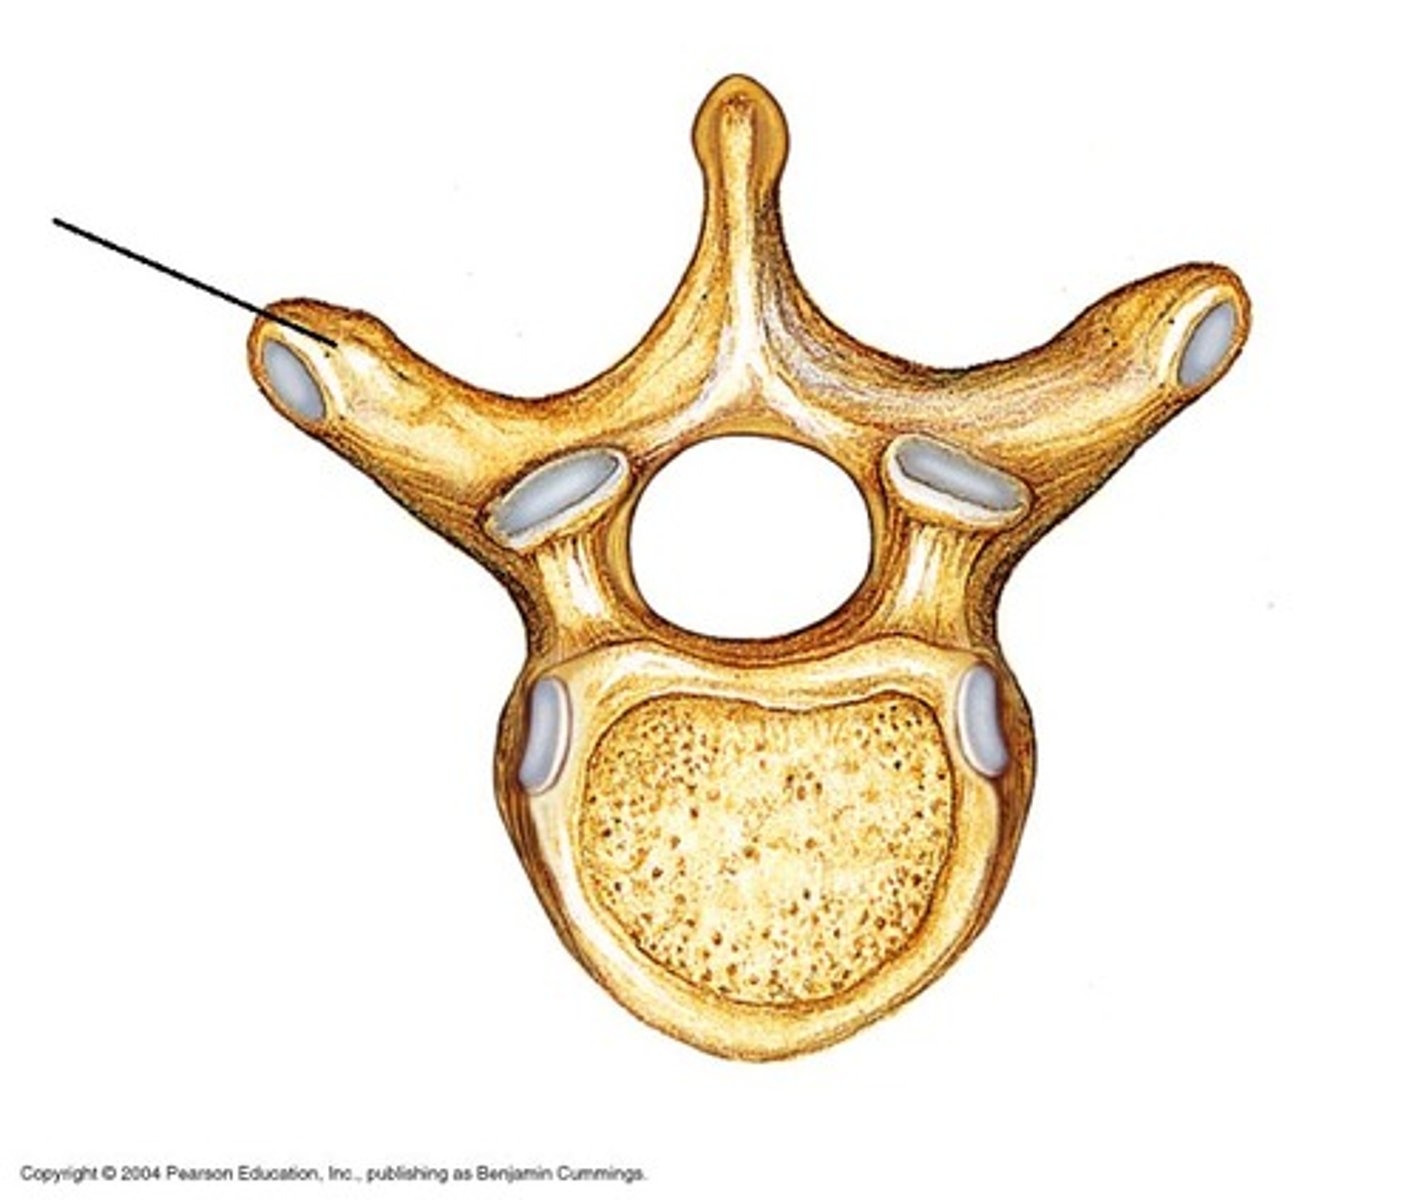

pedicle

body of vertebra

spinous process

transverse costal facet

rib articulation (attachment) ONLY FOUND IN T1-T12

what is the purpose of the transverse costal facets

transverse costal facets (articulations) where ribs attach to

what differenciates the T spine vertebra